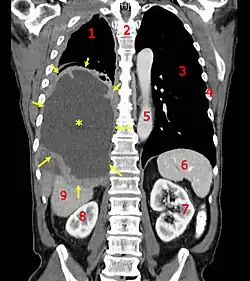

| CT scan showing a left sided mesothelioma with an enlarged mediastinal lymph node | |

More than 80% of mesothelioma cases are caused by exposure to asbestos.[3] The greater the exposure, the greater the risk.[3] As of 2013, about 125 million people worldwide have been exposed to asbestos at work.[13] High rates of disease occur in people who mine asbestos, produce products from asbestos, work with asbestos products, live with asbestos workers, or work in buildings containing asbestos.[3] Asbestos exposure and the onset of cancer are generally separated by about 40 years.[3] Washing the clothing of someone who worked with asbestos also increases the risk.[13] Other risk factors include genetics and infection with the simian virus 40.[3] The diagnosis may be suspected based on chest X-ray and CT scan findings, and is confirmed by either examining fluid produced by the cancer or by a tissue biopsy of the cancer.[2]

Imaging

Diagnosing mesothelioma is often difficult because the symptoms are similar to those of a number of other conditions. Diagnosis begins with a review of the patient's medical history. A history of exposure to asbestos may increase clinical suspicion for mesothelioma. A physical examination is performed, followed by chest X-ray and often lung function tests. The X-ray may reveal pleural thickening commonly seen after asbestos exposure and increases suspicion of mesothelioma.[15] A CT (or CAT) scan or an MRI is usually performed. If a large amount of fluid is present, abnormal cells may be detected by cytopathology if this fluid is aspirated with a syringe.[11] For pleural fluid, this is done by thoracentesis or tube thoracostomy (chest tube); for ascites, with paracentesis or ascitic drain; and for pericardial effusion with pericardiocentesis. While absence of malignant cells on cytology does not completely exclude mesothelioma, it makes it much more unlikely, especially if an alternative diagnosis can be made (e.g., tuberculosis, heart failure). However, with primary pericardial mesothelioma, pericardial fluid may not contain malignant cells and a tissue biopsy is more useful in diagnosis.[11] Using conventional cytology diagnosis of malignant mesothelioma is difficult, but immunohistochemistry has greatly enhanced the accuracy of cytology.